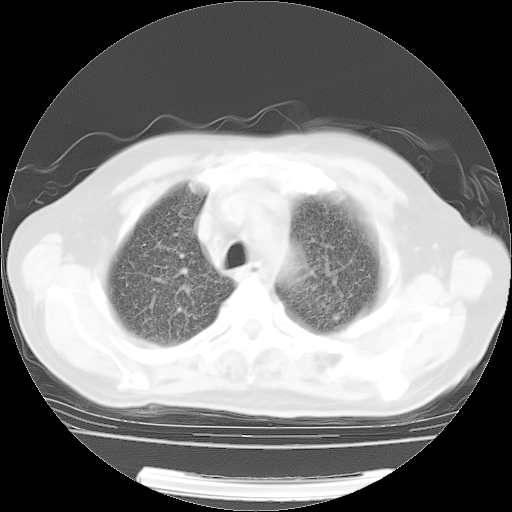

4月14日肺部CT

肺部CT平扫未见异常。